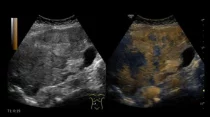

УЗИ с контрастным усилением ( CEUS ) является более точным и надежным, чем МРТ, для исследования определенных узлов печени и почек, согласно […]… далее